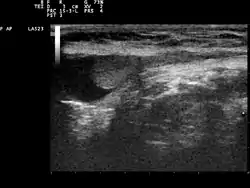

الخصية المعلقة أو الخصية الهاجرة أو الخصية غير النازلة أو الخصية المنكمشة أو خفاء الخصية[1] (بالإنجليزية: Cryptorchidism) هو اختفاء إحدى الخصيتين أو كلاهما من كيس الصفن و وجودهما في الحوض الذكري، ويعتبر هذا الخلل من أشهر العيوب الولادية في الجهاز التناسلي الذكري.